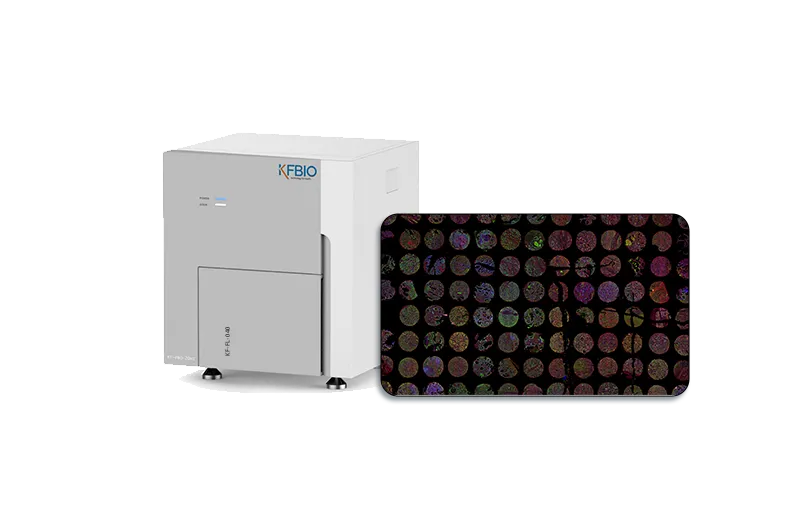

KF-FL-005

Digital Pathology 5

Slides Scanner fluorescence

Fast, High-precision,Stable, Clear

Scientific research, clinic,

tumor micro environment

KF-FL-020

Digital Pathology 20 Slides Scanner (Fluorescence)

Fast, Stable, Clear

Scientific research, clinic, tumor microenvironment

KF-FL-120

Digital Pathology 120

Slides Scanner fluorescence

High-throughput, Fast, Stable,

Continuous scanning

Scientific research, clinic,

drug target validation

KF-FL-400

Digital Pathology 400

Slides Scanner fluorescence

High-throughput, Fast, Stable,

Continuous scanning

Scientific research, clinic,

FISH analysis, molecular typing